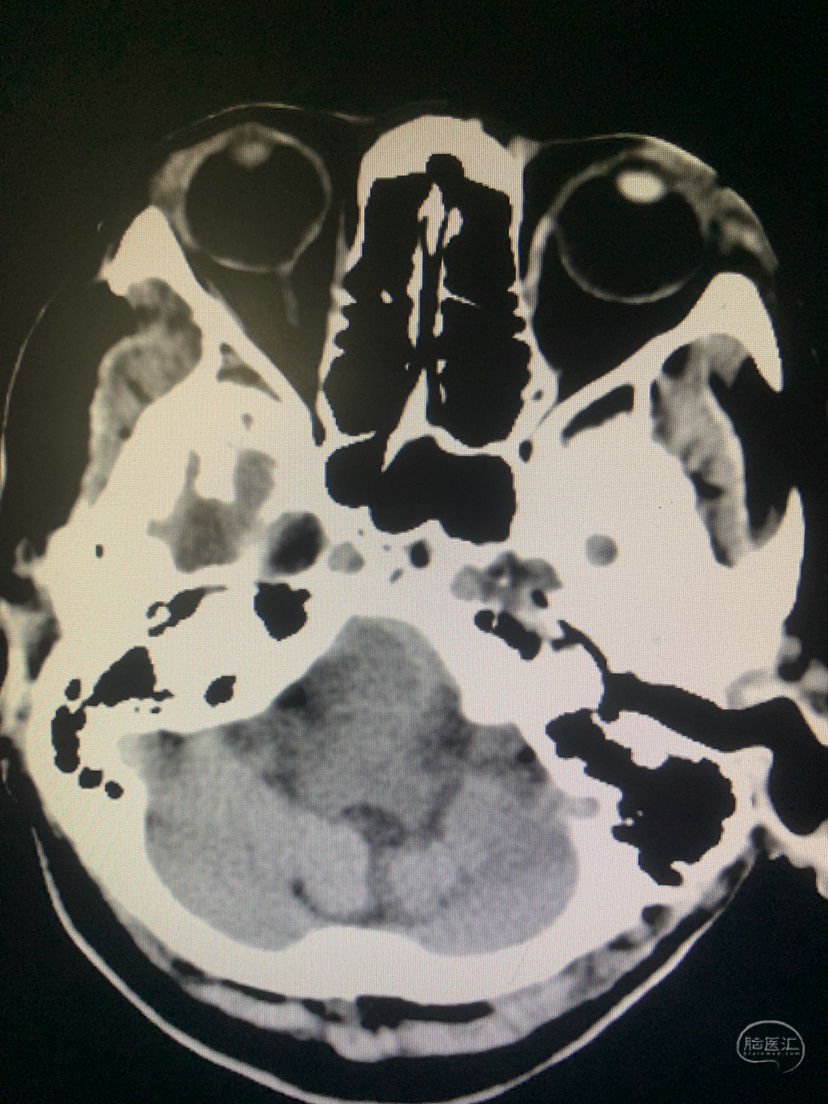

术前CT

术后CT